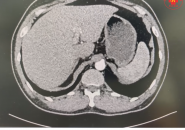

- Theo dõi bằng CT hoặc MRI